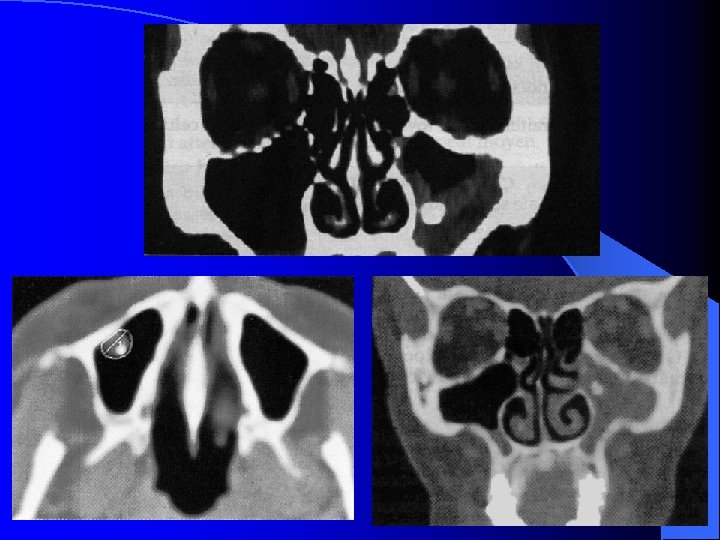

IMAGERIE DES CAVITES RHINO SINUSIENNES TDM FACIALE Coupes coronales, frontales et sagittales

MALADIES INFECTIEUSES RHINO SINUSIENNES SINUSITE MAXILLAIRE CHRONIQUE IMAGERIE Radiographies standard Blondeau (nez-menton-plaque): CE, Niveaux hydro-aérique Panoramique dentaire: Etat bucco-dentaire, signes unilatéraux TDM crânio-faciale IRM crânio-faciale

MALADIES INFECTIEUSES RHINO SINUSIENNES SINUSITE MAXILLAIRE CHRONIQUE IMAGERIE